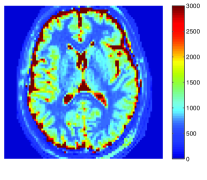

In MRI, data is acquired in the Fourier domain of the spatial image (a.k.a. k-space). The acquisition time of a high resolution, single contrast 3D MRI lasts a substantial amount of time. Since MRF is based on rapid acquisition of hundreds of different contrasts, severe under-sampling is performed in k-space to obtain the temporal resolution required for MRF. Figure 1 demonstrates the effect of fully sampled versus under-sampled data, acquired with spiral trajectories and recovered using the inverse non uniform fast Fourier transform (NUFFT) Fessler and Sutton [2003]. It can be seen that the under-sampled data is blurred and introduces aliasing artifacts. Figure 2 illustrates the noise and under-sampling artifacts of a representative brain voxel intensity as function of time, where the data is acquired with an MRF sequence based on fast imaging with steady state precession (FISP) Jiang et al. [2015]. Clearly, under-sampling also introduces a substantial level of noise in the time domain. In addition, MRF uses a dictionary with discrete values, while QMRI values are continuous. This leads to quantization error, depending on the values represented in the dictionary.

Figure 6 shows the resulting maps for the recovery of T1, T2 and PD obtained with the various algorithms against the reference (left). The corresponding error maps of each method versus the reference are shown in Fig. 7. To allow detailed view of the reconstruction results for the reader, Fig. 6 shows a zoomed region for each map.

It can be seen that both FLOR and MBIR-MRF outperform BLIP reconstruction results, when using 5% of sampled data by utilizing the low rank property. In addition, FLOR provides a lower error compared to MBIR-MRF. The details in the FLOR maps are comparable to those obtained by the original MRF algorithm using 100% of the noise-free data. Due to the very low sampling ratio in our experiments (measured as the number of samples divided by the number of pixels in the image), conventional MRF using 5% of the data did not provide valuable reconstruction results and is therefore omitted in this analysis.

We next implemented the MF improvement described in Section II.D. The results are shown in Fig. 8, with corresponding error maps in Fig. 9. These figures compare the recovery maps of FLOR without (FLOR I) and with (FLOR II) the proposed improvement. It can be seen that FLOR II improves the results of FLOR I and produces a smoother solution which better fits the reference maps.